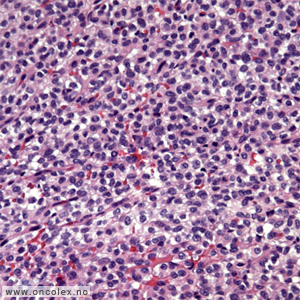

Ewings sarkom, PNET (primitiv neuroektodermal tumor) og Askins tumor hører til en familie av maligne småcellete svulster ("the Ewing family of tumours") som viser varierende grad av neuroektodermal differensiering. Tumor kan være lokalisert i både bløtvev og benvev.

Histologisk ses små runde celler med sparsomt cytoplasma. Cellene er glykogenholdige, noe som kan påvises med PAS histokjemisk. Enkelte tilfeller kan vise mer pleomorfe celler. Det er ingen matrixproduksjon. Rosetter kan påvises og er relatert til neuroektodermal differensiering. Tumor er per definisjon høygradig malign og noen gradering er ikke meningsfull.

Det er en rekke differensialdiagnoser som for eksempel malignt lymfom, rhabdomyosarkom, småcellet osteosarkom, mesenkymalt kondrosarkom, småcellet karsinom og nevroblastom. Man utfører ofte en rekke spesialundersøkelser med immunhistokjemisk analyse, cytogenetisk og molekylærpatologisk (RT-PCR og FISH) undersøkelse, og av og til elektronmikroskopisk undersøkelse.

Immunhistokjemisk kan en se positivt funn for vimentin, CD99 (sensitiv, men ikke spesifikk) og FLI-1, men negativt funn for et panel med antistoffer med tanke på å utelukke andre svulster. PNET har positivt funn for enkelte neuroektodermale markører som synaptofysin, protein S-100 og kromogranin.

Histologisk bilde av Ewings sarkom. |